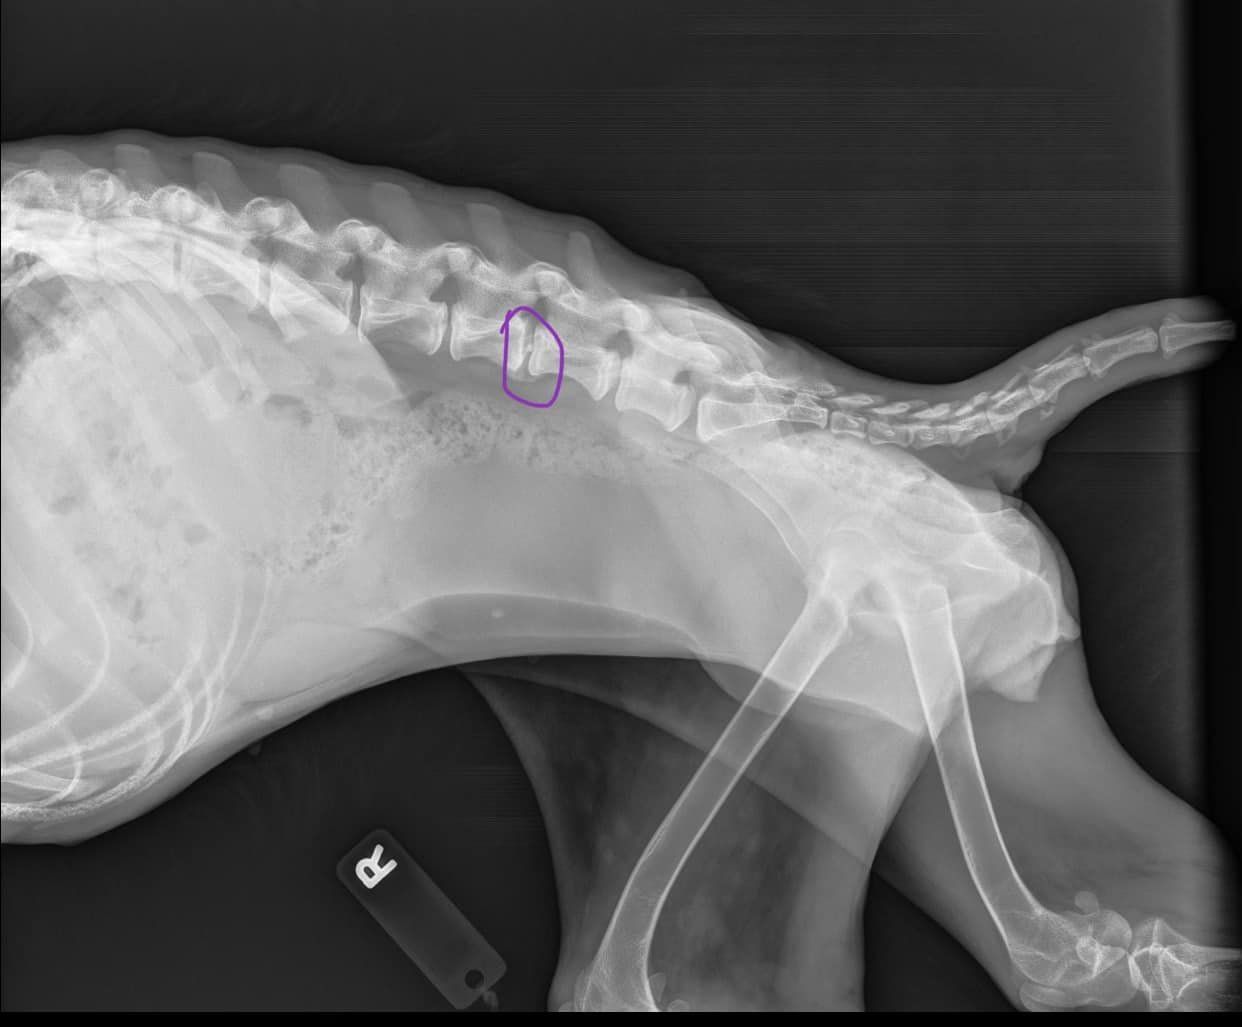

Putting her in a rear wheelchair very well could make her spine worse because of the placement of the injury and the way it has healed itself. She is 100% weight bearing on her front end.